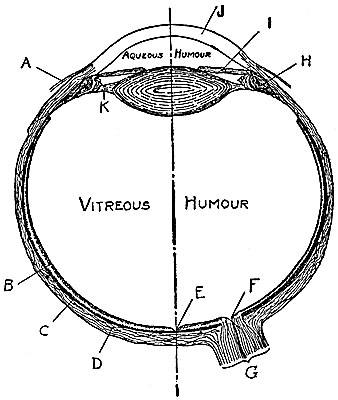

Fig. 1.—Principal parts of the eye.

A, Conjunctiva; B, Retina; C, Choroid; D, Sclera;

E, Fovea; F, Blind Spot;

G, Optic Nerve;

H, Ciliary Muscle; I, Iris; J, Cornea; K, Ligament.

The eye is approximately a spherical shell transparent at the front portion and opaque (or nearly so) over the remaining eighty per cent of its surface. The optical path consists of a series of transparent liquids and solids. The chief details of the structure of the eye are represented in Fig. 1. Beginning with the exterior and proceeding toward the retina we find in succession the cornea, the anterior chamber containing the aqueous humor, the iris, the lens, the large chamber containing the vitreous humor, and finally the retina. Certain muscles alter the position of the eye and consequently the optical axis, and focusing (accommodation) is accomplished by altering[Pg 15] the thickness and shape, and consequently the focal length, of the lens.

The structure of the retina plays a very important part in vision and accounts for various illusions and many interesting visual phenomena. The optic nerve spreads out to form the retina which constitutes the inner portion of the spherical shell of the eye with the exception of the front part. Referring again to Fig. 1,[Pg 21] the outer coating of the shell is called the sclerotic. This consists of dense fibrous tissue known as the “white of the eye.” Inside this coating is a layer of black pigment cells termed the choroid. Next is the bacillary layer which lines about five-sixths of the interior surface of the eye. This is formed by closely packed “rods” and “cones,” which play a dominant role in the visual process. A light-sensitive liquid (visual purple) and cellular and fibrous layers complete the retinal structure.